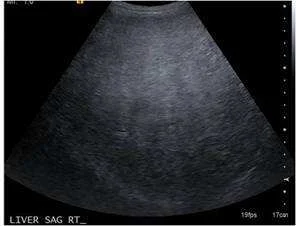

【109-1 醫學(三) 第74題】

32歲女性,主訴食慾不振和倦怠感,經超音波與未施打對比劑腹部電腦斷層檢查後如圖,最有可能的診斷為?

詳解

破題關鍵

這題的解題核心在於辨識超音波和未施打對比劑的電腦斷層影像上,肝臟實質的典型變化,尤其是肝臟回音增強和密度降低,這些都是脂肪肝的明確徵象。

選項拆解

-A:錯在阻塞性黃疸的影像特徵通常是膽管擴張,或可見膽管內結石或腫瘤等阻塞物,這些在圖中並未看到。